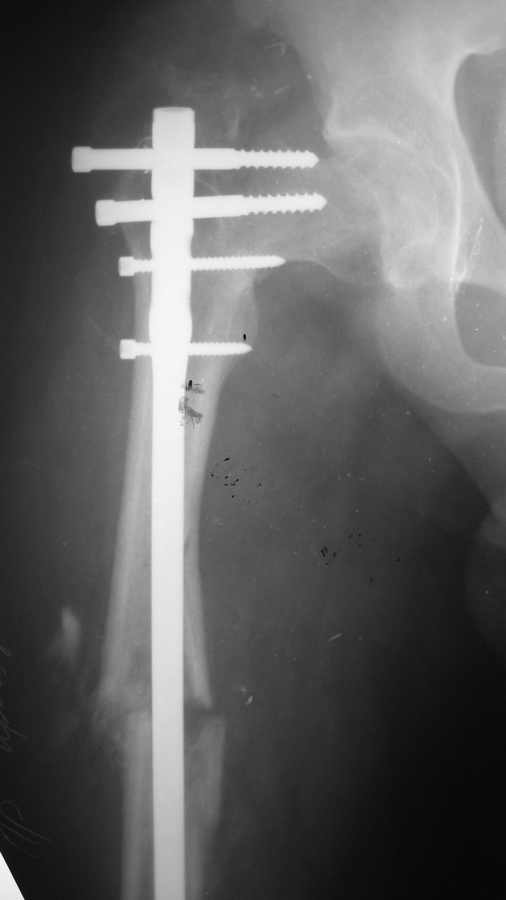

Парень, 23 года, исходно здоров.25 октября 2008 вследствие ДТП политравма (мотоциклист):

оскольчатый диафизарный перелом правой бедренной кости + чрезвертельный перелом правого

бедра ( был диагностирован во время операции, был без смещения). Перелом двух лодыжек и

перелом пятки слева.

По скорой помощи через 6 часов после аварии произведено оперативное лечение:

интрамедулллярный остеосинтез правого бедра + фиксация чрезвертельного перелома 3-мя

винтами. Металлоостеосинтез голеностопного сустава слева, пятка не оперировалась. После

операции через 14 часов развилась жировая эмболия легких, тяжелая форма, которая

разрешилась благополучно. При контрольной рентгенографии через 1 месяц отмечено смещение

в области чрезвертельного перелома,варусная деформация. Сейчас прошло 6 мес. Идет

медленная консолидация переломов. Необходима реконструктивная операция. Вопрос: какая

(метод?), когда, ведущие клиники. Общее состояние сейчас удовлетворительное, жалоб нет.